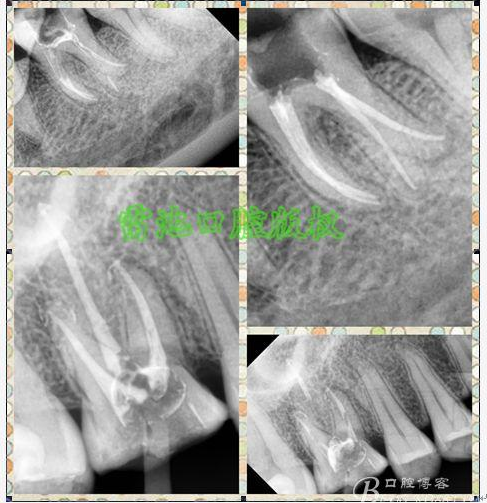

E 、X線影像學的檢查研判能力: 這點不需要強調太多,對于普通的非CBCT的二維影像對醫(yī)生讀片能力有一定的要求,有個逐步提高的過程,非一蹴而就,需要學會把二維的X線影像與三維的解剖結構進行良好的對應結合,對于某些鈣化的髓室底,應通過想象把根管口的分布、根管的走向以及各種變化通過想象投射到對應的髓室底上;

G:找尋MB2的問題:

1、查閱各種文獻,MB2的發(fā)生率在52-96%之間,治療時遺漏是上頜磨牙根管治療失敗的主因,2、一般位于MB1根管口與腭根管口方向的0.5-5mm范圍內,而大多數都位于MB舌側的1-3mm處,其中2mm以內占85.7%,3、MB1-P根管口連線與MB1-MB2根管口的連線夾角大部分(74.3%)在30度以內;4、MB2的尋找大部分需要去除相應部位的牙本質;5、當找到的MB根管口呈“長線型”且有深色凹線向舌側,或者找到的MB根管口明顯偏頰多提示有MB2的可能;6、DOM(牙科手術顯微鏡)的使用有助于找尋MB2;